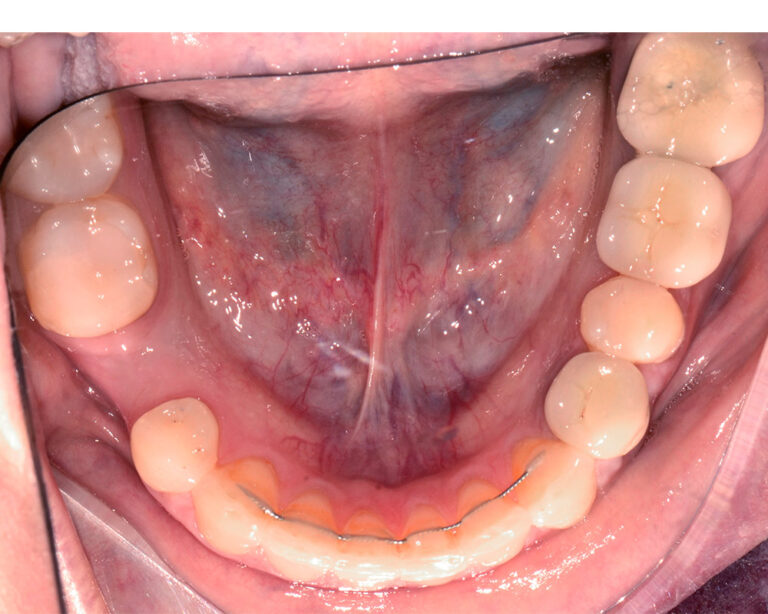

Кейс 23

Иванова Екатерина Сергеевна

Количество кап ВЧ 24

Количество кап НЧ 24

ДО

ПОСЛЕ